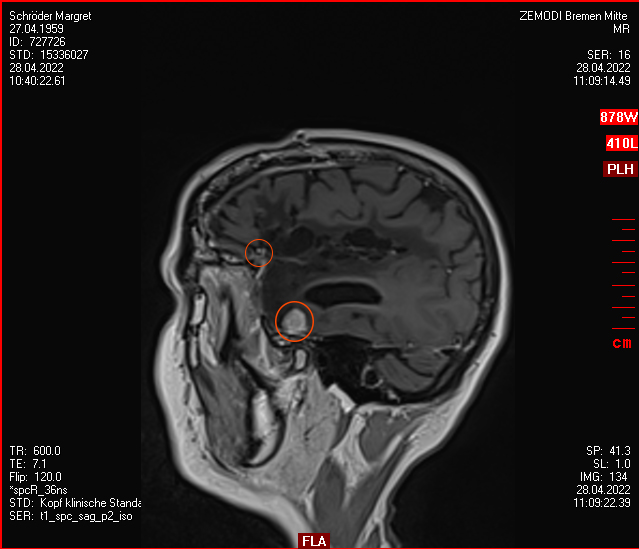

Heute war der Termin beim Chirurgen, leider schon um 9:00 Uhr und natürlich wollte ich die knapp 20 km mit dem Rad zurück legen, Stephan wollte gerne mitkommen. Leider war die bereits abgegebenen CD nicht eingelesen worden und so musste erstmal die Datenverarbeitung arbeiten und wir warten, bis wir eine Auskunft bekommen konnten. Fazit: Der bestehende Tumor ist kaum gewachsen. Aber es hat sich leider ein 2. Fund ergeben, sehr klein aber deutlich sichtbar. Aber Maßnahmen sind erstmal nicht notwendig.

Nun ist der große Tumor schon sechs Jahre nicht mehr im Kopf. Dafür ein paar kleine Rezidive, unter regelmäßiger Kontrolle/ Beobachtung.